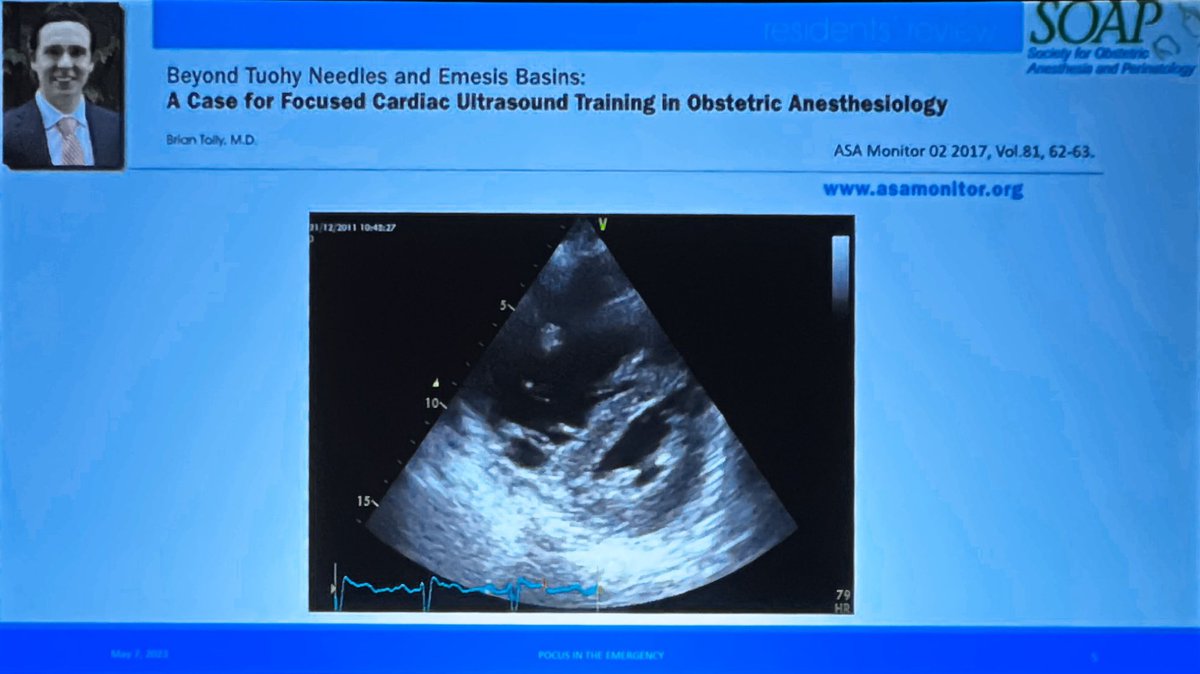

Dr Clemens Ortner, MD continues the #Solshnider track, speaking on #POCUS in the #OBAnes emergency - How can we guide care? #SOAPAM2023 Image

Case 1. Why was focused TTE not being used more widely in #OBAnes? #SOAPAM2023 ImageImageImageImage

Learning objectives. #POCUS #OBAnes #SOAPAM2023 Image